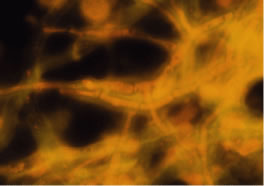

The preferred stains for identification of hyphal fragments and yeasts in smears of corneal scrapings are acridine orange and calcofluor white.33, 34, 35, 36, 37, 38 Each of these techniques requires use of a fluorescent microscope. The optical activity of acridine orange is due to the binding of the dye to deoxyribonucleic acid (DNA) of bacteria, fungi, and amoebae to form a green-fluorescing complex. Acridine orange is more sensitive than the Gram stain in detecting microorganisms in clinical specimens36 and is, therefore, a rapid and sensitive method for screening all corneal smears in suspected infectious keratitis. If microorganisms are detected by acridine orange stain, the slide can be washed and stained with Gram or other specific stains. The preferred procedure is to fix the smears in 95% methanol for 5 to 10 minutes, apply the acridine orange dye (number 3336-75)* for 2 minutes, rinse the slide with tap water, blot dry, and examine by fluorescent microscopy. Hyphal fragments stain yellow-orange or green, and yeasts stain brilliant orange (Fig. 22).

Fig. 22. Curvularia senagalensis keratitis. Fluorescent microscopy. Direct smear of corneal scraping stained with acridine orange. Note the distinction of the septate hyphal fragments. (× 630.)